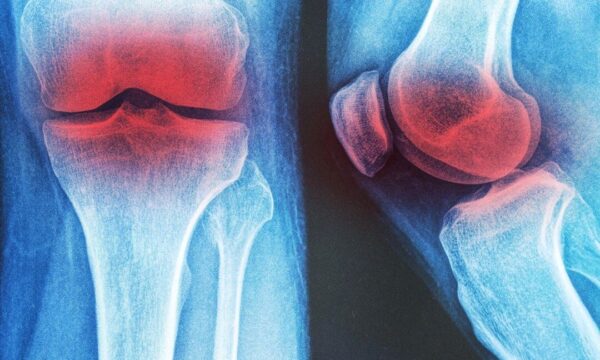

膝の変形性関節症に効く 3つの非薬物療法

変形性関節症は治せる? 700の遺伝子が導く未来医療

変形性関節症が引き起こすリスクとは? 慢性疾患の連鎖を防ぐ予防法